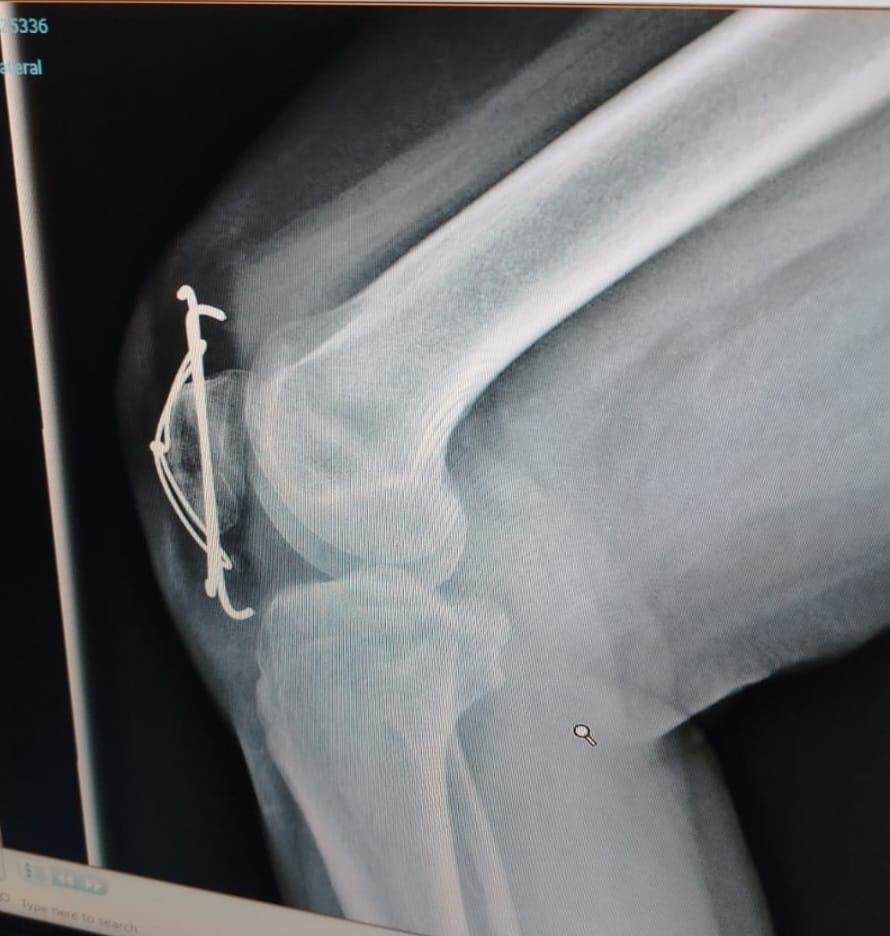

Diagnosticul? Fractură cominutivă de rotulă, operată cu broșe K și sârmă tip hobanaj. O intervenție complexă, ce a necesitat nu doar tratament chirurgical, ci și un program riguros de recuperare.